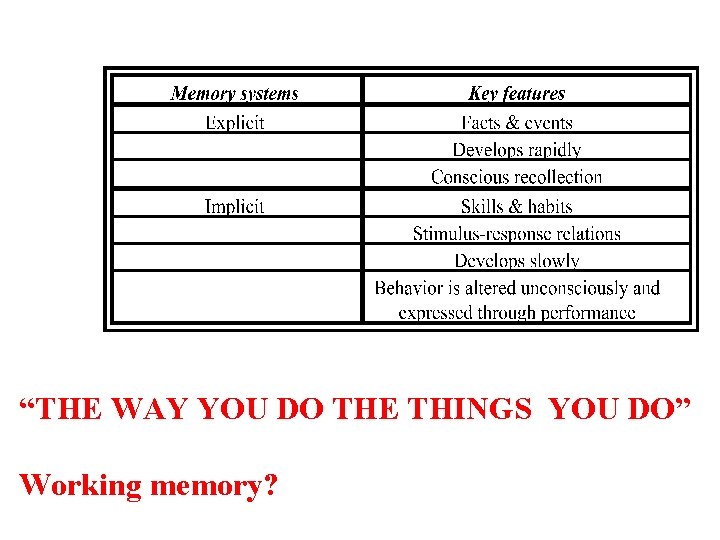

“THE WAY YOU DO THE THINGS YOU DO” Working memory?